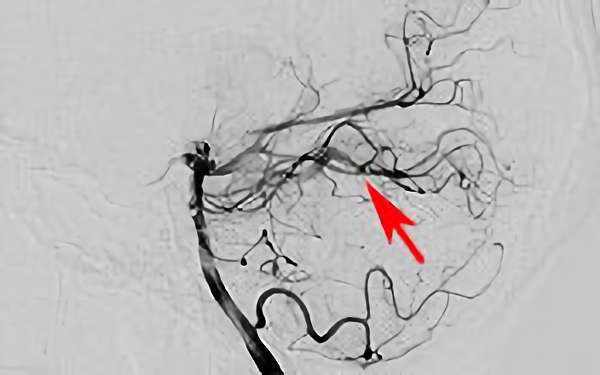

No.1620 手術後